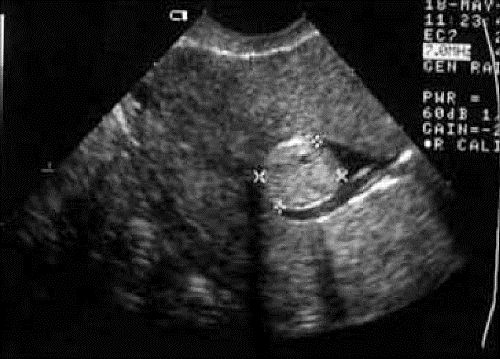

При осмотре шейки матки в зеркалах и при кольпоскопии легко диагностируются шеечная миома, расположена во влагалище, и фиброматозный узел рождается. Ультразвуковое исследование органов малого таза позволяет определить размеры, количество, локализацию, эхогенность, структуру узлов, установить наличие сопутствующей гиперплазии эндометрия, патологии придатков матки. Гистероскопию применяют для выявления подслизистых фиброматозных узлов, определения состояния эндометрия, в некоторых случаях используют гистеросальпингографию. Преимуществом гистероскопии является возможность выполнения одновременной биопсии эндометрия, удаление полипов и субмукозных узлов, резекцию эндометрия.